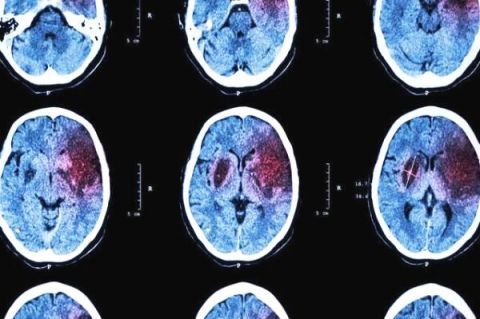

[分享]高血压患者吃降压药的同时加上这1物 有效预防血栓和中风

提到叶酸,估计大家第一时间想到的,是备孕时需要补充它。听说它可以避免宝宝出现神经缺陷,让宝宝更聪明,但至于为啥高血压会与叶酸扯上关系,又为啥很多人建议补充叶酸,估计大家还是一头雾水。实际上,这主要是因为一旦体内缺乏叶酸,会导致同型半胱氨酸(Hcy)升高,一旦患者同时还存在高血压问题,就会形成H型高血压(H是Hcy的缩写)。而这类高血压更容易出现中风问题,下面我们就来一起看看吧。

H型高血压会增加心脑血管疾病的风险。在导致心脑血管疾病上,高血压和高同型半胱氨酸(Hcy)具有明显的协同作用。

H型高血压:中国人更容易得

一直让中国医学界困扰的问题:中国高血压患者更容易中风!统计数据显示,尽管中国高血压人群的总胆固醇、LDL-c、肥胖以及糖尿病的情况比欧美国家好,但中风的发病率却显著更高。此外,当通过各种方法,将血压控制到相似水平时,中国高血压患者也依然更容易出现中风。

为解决这一疑惑,我国著名心血管疾病专家胡大一教授,潜心研究多年,最终发现:中国高血压患者,并发高同型半胱氨酸血症的概率要远超国外!

基于此,胡大一教授于2008年首次提出H型高血压的概念,即同时存在血同型半胱氨酸升高的高血压。这一结论在随后的国家高血压防治指南中被重视,并达成广泛共识。